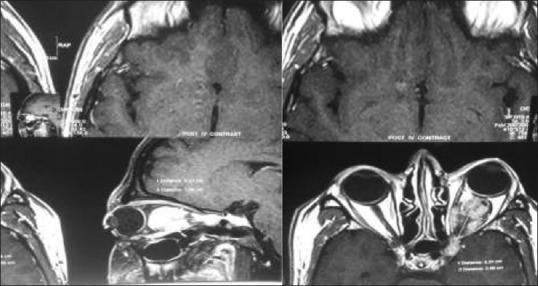

A 32-year-old man presented with axial proptosis of his left eye. Visual acuity and other ocular examinations were normal. Orbital magnetic resonance imaging revealed a well-defined fusiform retrobulbar lesion in the left orbit extending into the superior orbital fissure and left cavernous sinus measuring 43 mm × 21 mm × 19 mm and causing superomedial displacement of the optic nerve and axial proptosis. The patient was scheduled for surgery, and gross total excision was done. Postoperatively, the patient developed total third nerve palsy. Pre and postoperative third nerve deficit confirmed the origin of the tumor from the oculomotor nerve. Histopathological examination revealed schwannoma.

一名32岁男性出现左眼轴向性眼球突出。视力及其他眼部检查均正常。眼眶磁共振成像显示左眼眶内有一个边界清晰的梭形球后病变,延伸至眶上裂和左侧海绵窦,大小为43 mm×21 mm×19 mm,导致视神经向眶上内侧移位及轴向性眼球突出。患者被安排接受手术,并进行了肿瘤全切。术后,患者出现完全性动眼神经麻痹。术前和术后的动眼神经功能缺损证实了肿瘤起源于动眼神经。组织病理学检查显示为神经鞘瘤。